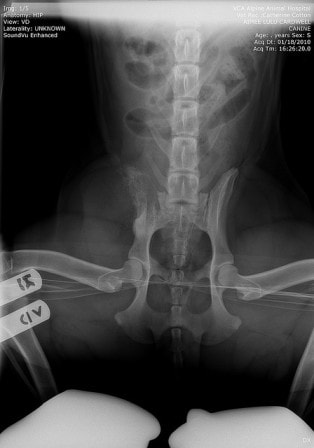

Proximal Radial And Distal Humeral Osteosarcoma In 12 Dogs

Proximal Radial and Distal Humeral Osteosarcoma in 12 Dogs Twelve dogs were diagnosed with osteosarcoma of the proximal radius or distal humerus from ... Retrieve Content

Bone Cancer In Dogs - YouTube

Brodie was diagnosed with bone cancer of his left front leg. This video shows the x rays, pain relief, and how he looks the next day. Amputation has a 10% cure rate and on average gives pets an exrtra 6 months. Let's hope for the 10% ... View Video

Bone Cancer (in Dogs) - YouTube

"My rotty has had a limp for about a week. I took her to the vet, they took xrays and found bone cancer. Is there anything else it could be?" Your Hometown V "My rotty has had a limp for about a week. I took her to the vet, they took xrays and found bone cancer. ... View Video